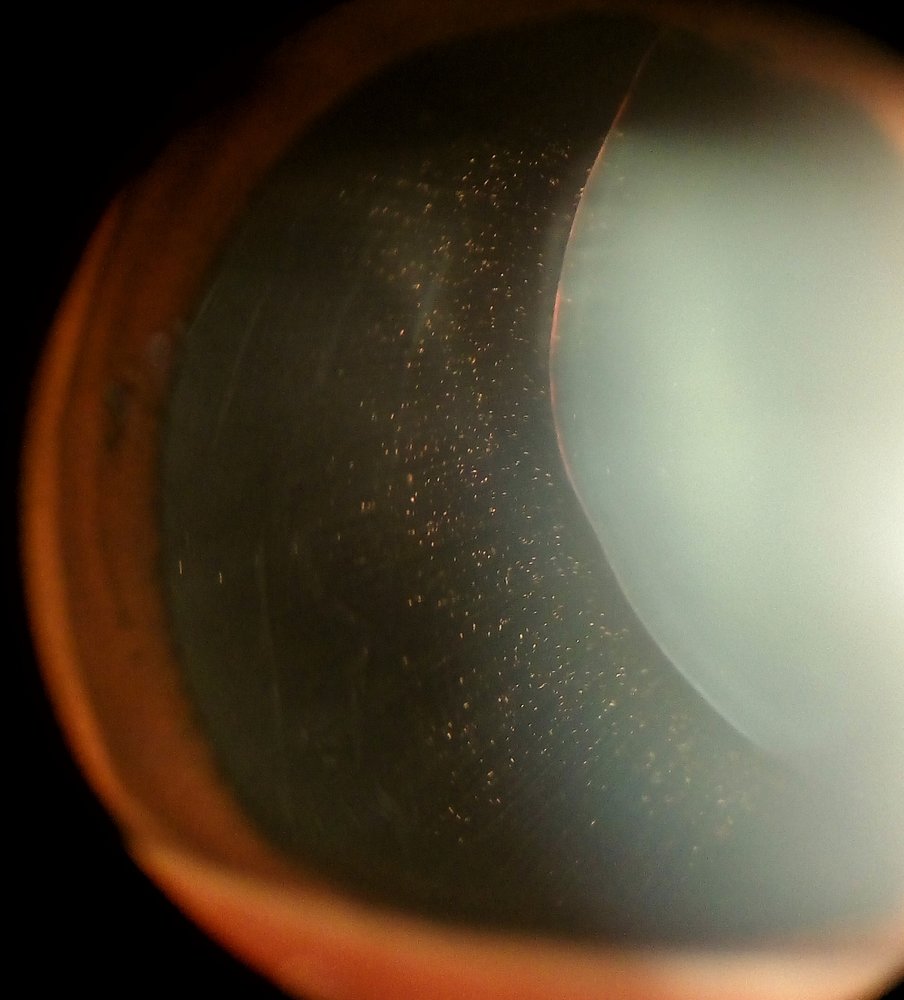

• Luxation of the lens

• Completely displaced lens; outside of the hyaloid fossa, in the anterior chamber, on the retina, or free-floating in the vitreous

• Severe visual impairment due to a change in total refractive power

• Diagnostics: visual acuity, slit lamp examination, retinoscopy, and ultrasound of the eye

• Ophthalmological assessment may include visual acuity testing, slit lamp examination, retinoscopy, ultrasound of the eye, and tonometry

• Findings include:

• The lens may dislocate into the vitreous or the anterior chamber